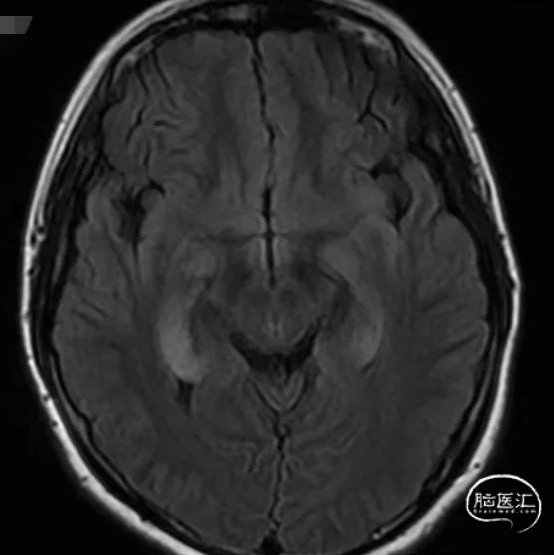

头颅MRI

1

2

3

4

头颅MR:双侧海马及杏仁核,双侧岛叶,左侧颞叶,双侧扣带回异常信号影。